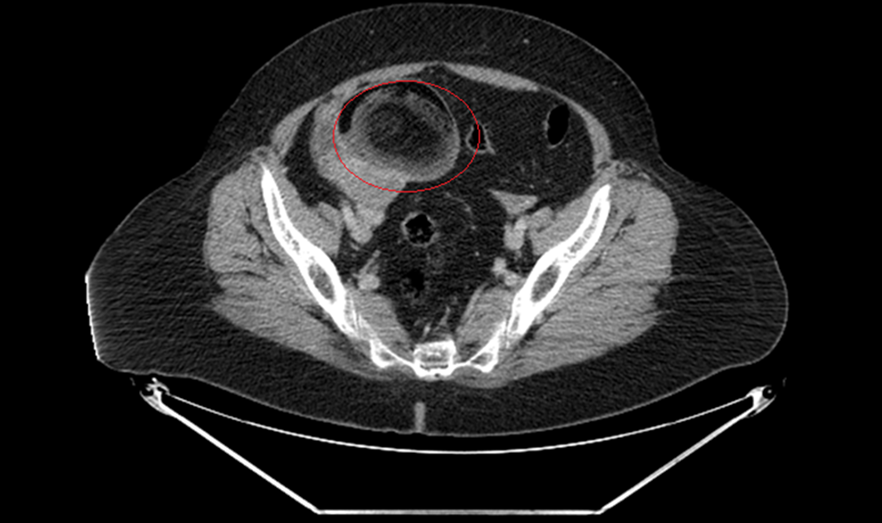

Malignant Transformation of Ovarian Mature Teratoma: About a Case and Literature Review

Nisrine Acharfi, Karima Oualla, Hajar Ouahbi, Zineb Benbrahim, Samia Arifi, Hind EL Fatemi, Meryem Boubou, Chahrazed Bouchikhi, Abdelaziz Banani, Nawfel Mellas

International Journal of Innovative Research in Medical Science·November 10, 2019